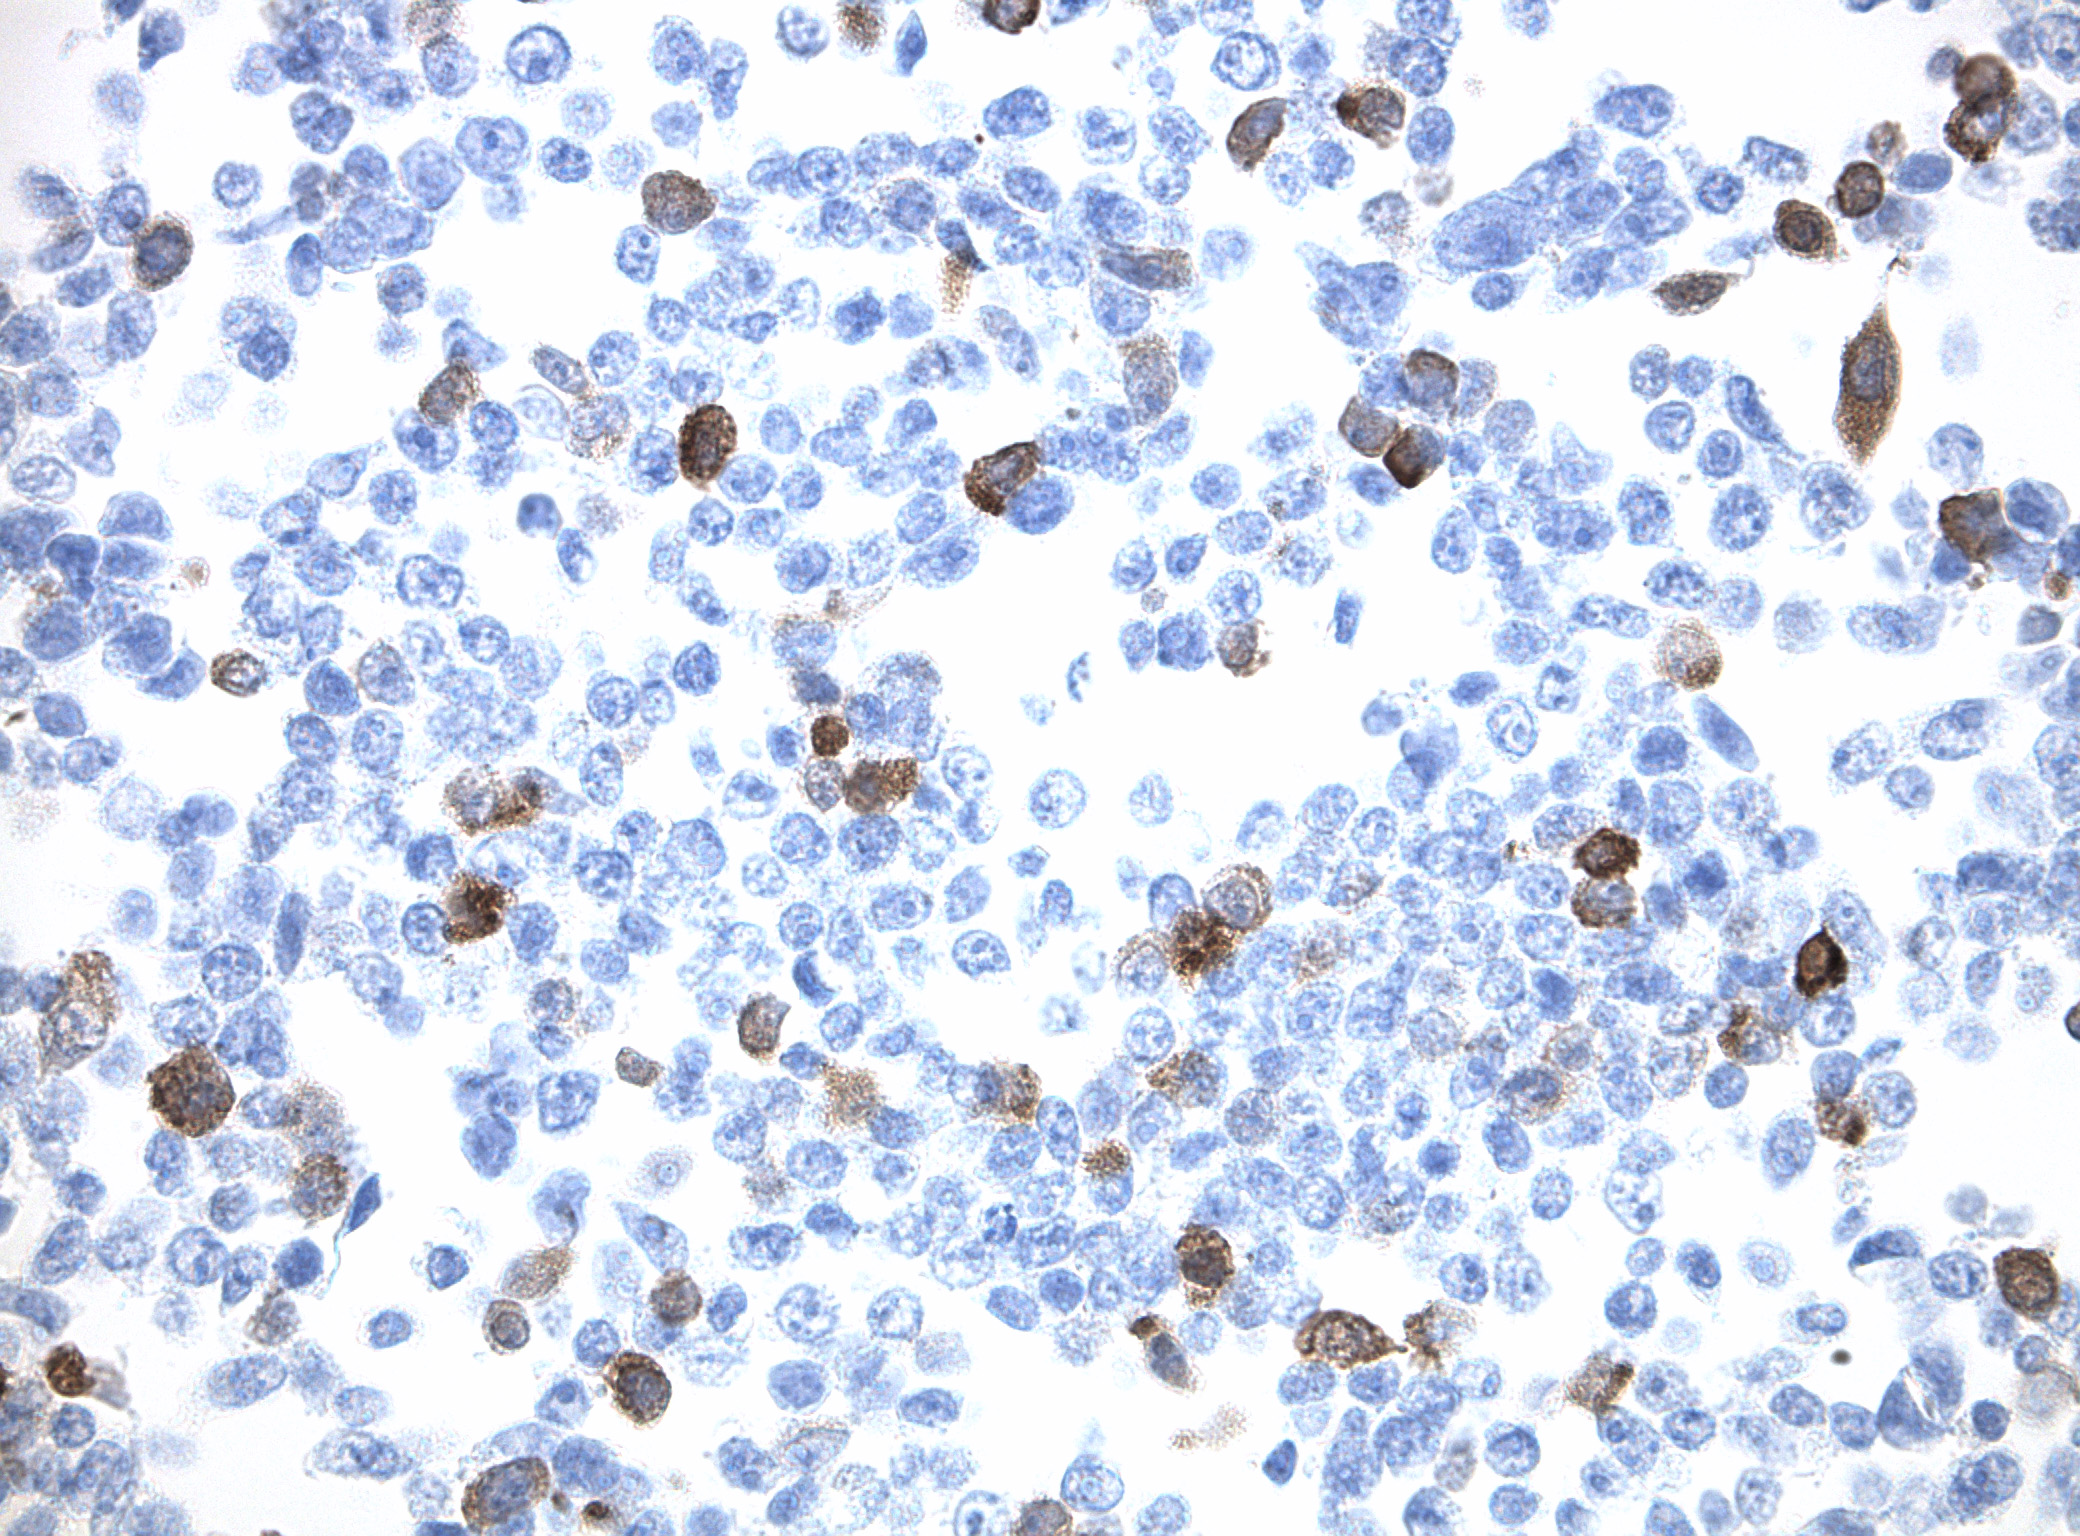

IDH1 (R132H) Mutant-Specific Antibody Screening, Validation, and Specificity

CytoSections enables identifying the right antibody for your research. See how CytoSections, featuring WT or mutant IDH1 (R132H) protein, helped screening and validation of specific antibody against the mutant IDH1 (R132H).

CytoSections |

IDH1 (WT) |

IDH1 (R132H) |

IDH1 (WT) |

IDH1 (R132H) |

|

IDH1 (R132H) Antibody |

Reactivity |

None |

Strong |

None |

Mild |